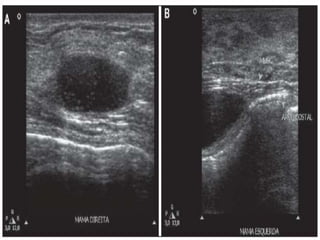

Além da mamografia existem ainda outros meios de

diagnóstico de câncer de mama além da mamografia, tais

como ressonância magnética, ultrassonografia e

tomossíntese.

ULTRASSONOGRAFIA

Além da mamografiaexistem ainda outros meios de diagnóstico de câncer de mama além da mamografia, tais como ressonância magnética, ultrassonografia e tomossíntese.